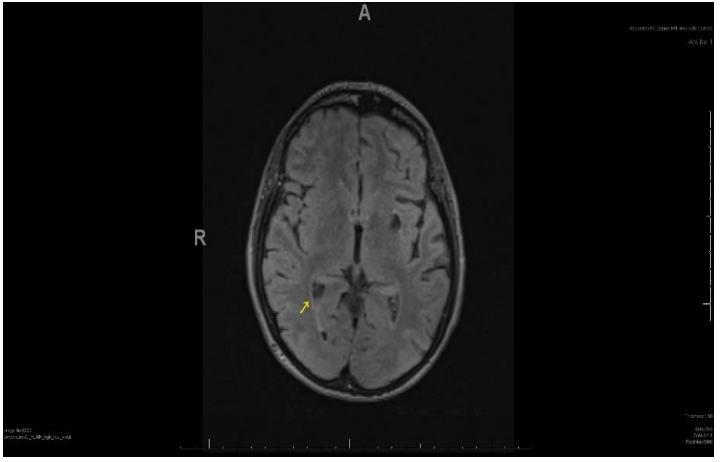

We requested an MRI Head to further guide treatment. It revealed appearances in-keeping with the diagnosis of meningitis. An abnormal signal was noted within the occipital right lateral ventricle, the extra-axial spaces of the frontal convexities and to a lesser degree in the interhemispheric fissure. This was most likely thought to be secondary to infected CSF or pus (Figure 1). The scan also revealed superficial siderosis with cerebellar atrophy (possibly secondary to previous head injuries) further explaining the pre-existing ataxic gait.